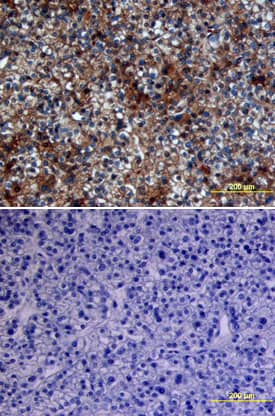

Glypican 3 antibody in Human Breast by Immunohistochemistry (IHC-P).

Glypican 3 in Human Breast.

Glypican 3 was detected in immersion fixed paraffin-embedded sections of human breast using 5 µg/mL Sheep Anti-Human Glypican 3 Antigen Affinity-purified Polyclonal Antibody (Catalog # AF2119) overnight at 4 °C. Tissue was stained with the Anti-Sheep HRP-DAB Cell & Tissue Staining Kit (brown; Catalog # CTS019) and counterstained with hematoxylin (blue). View our protocol for Chromogenic IHC Staining of Paraffin-embedded Tissue Sections.